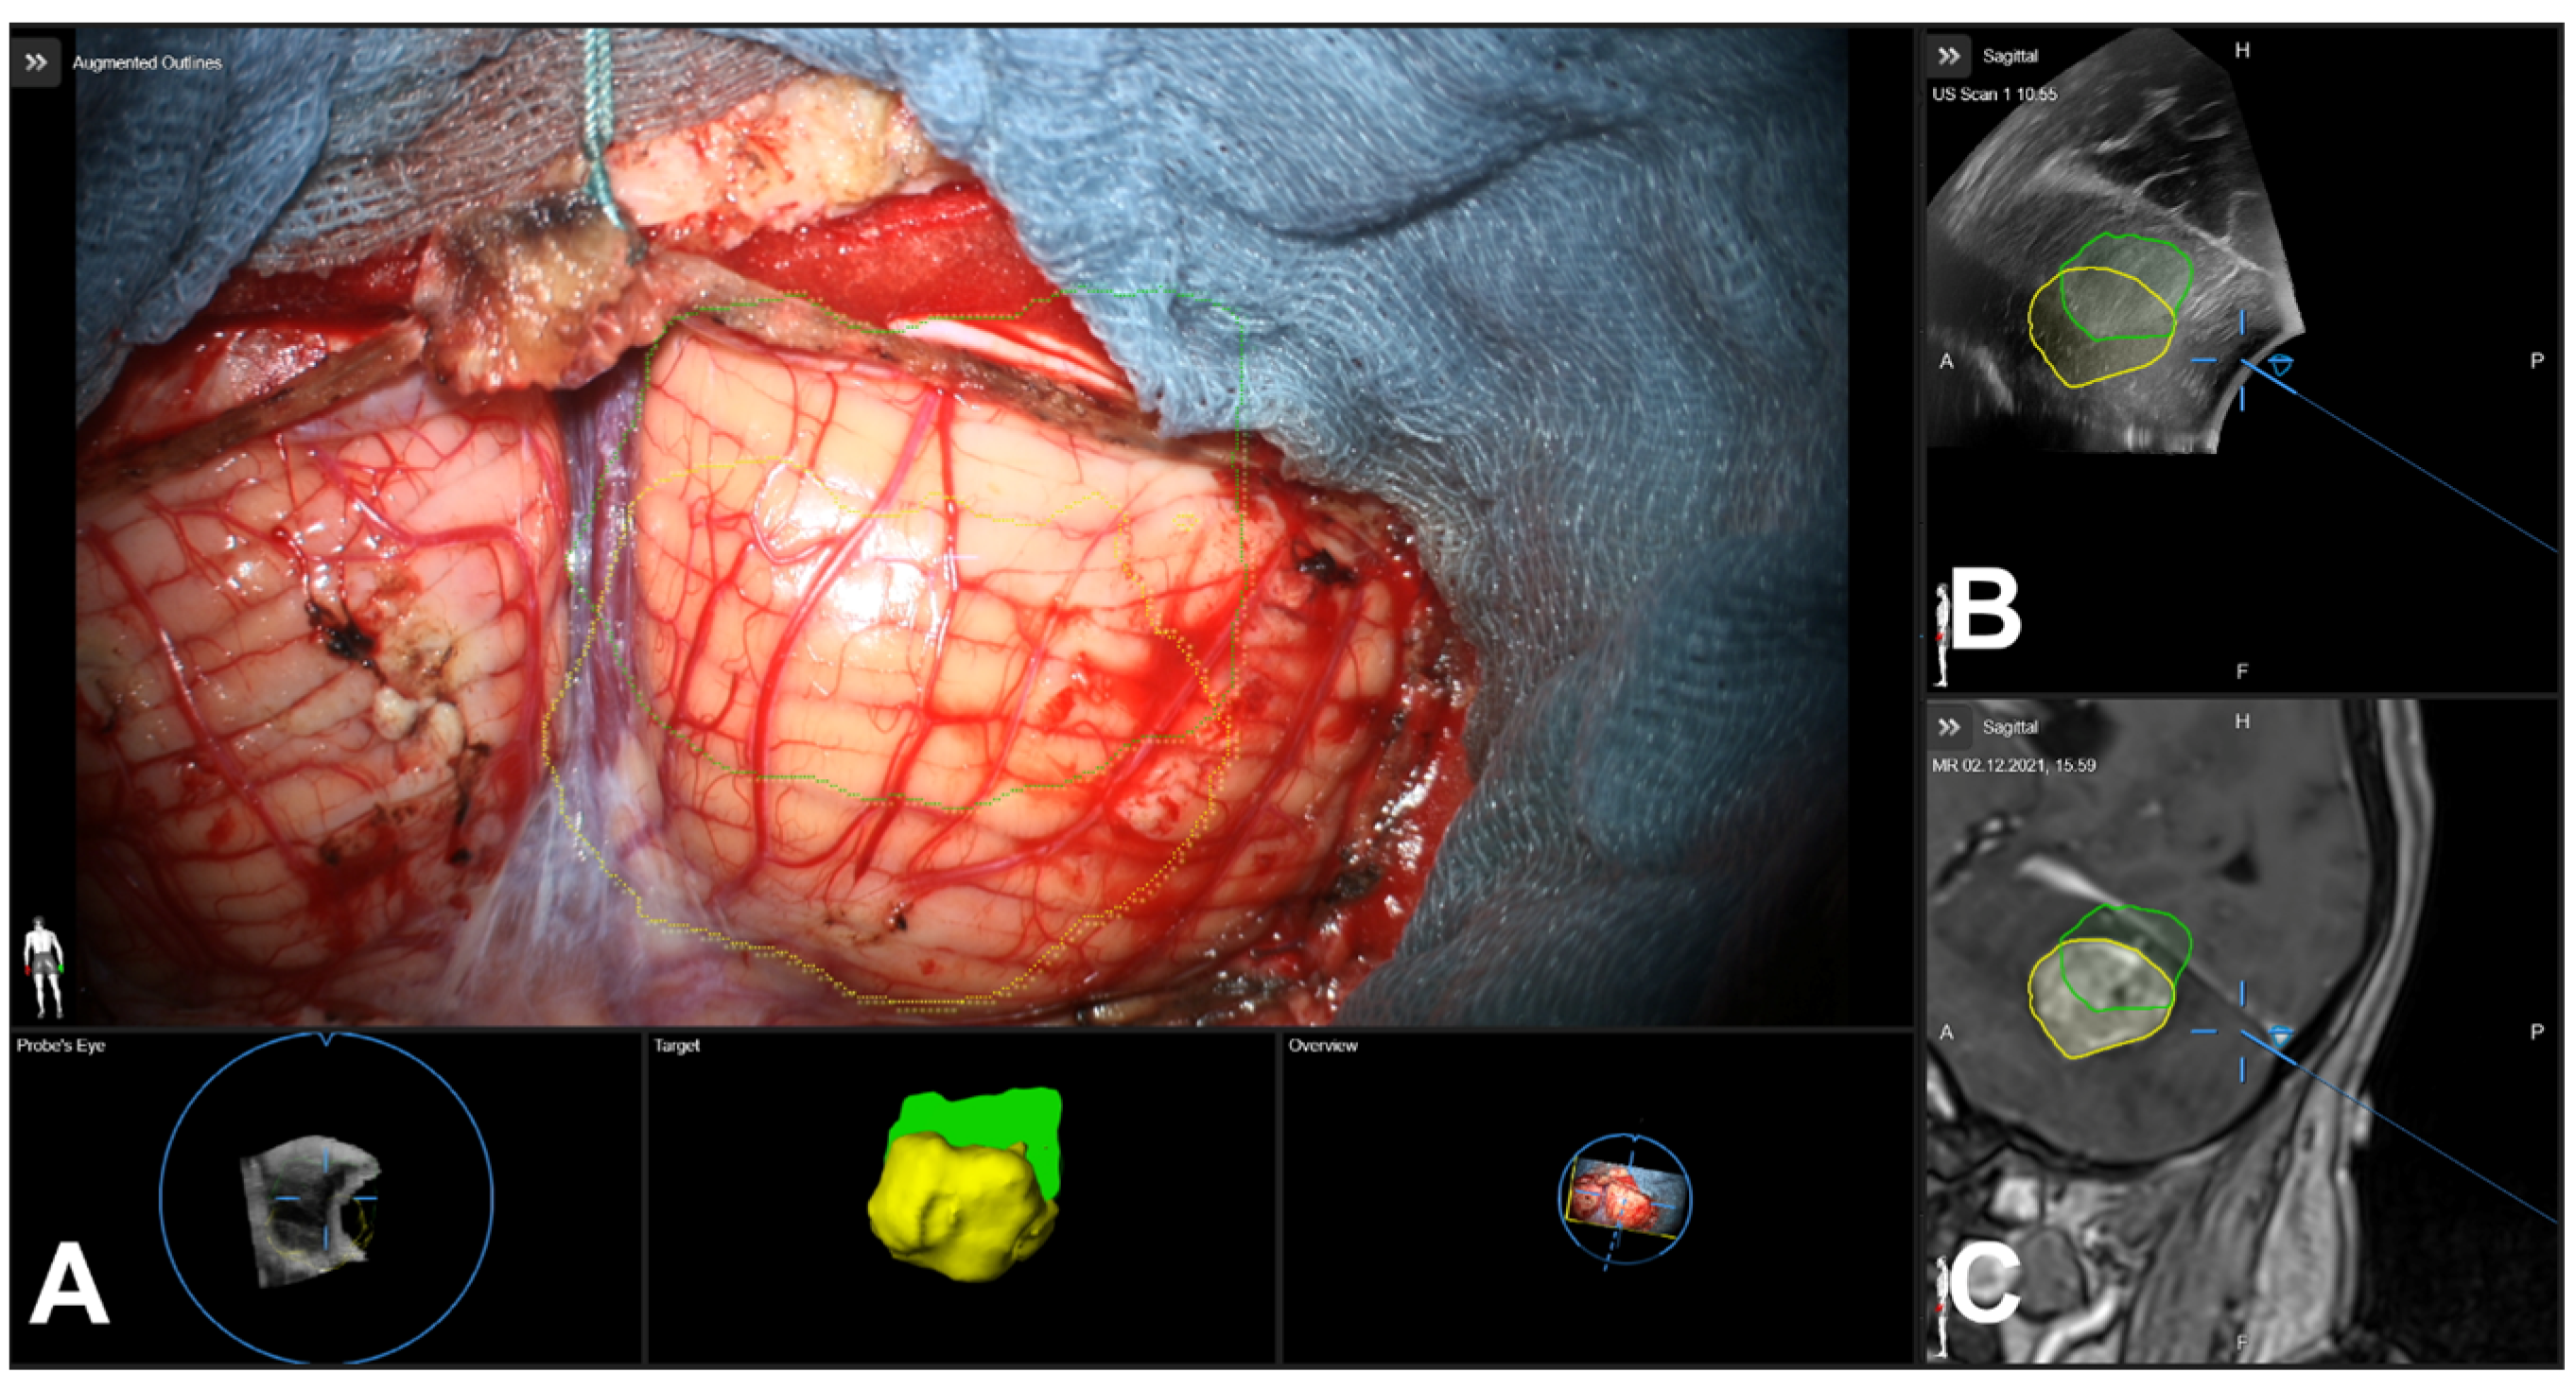

3.5. Illustrative Cases